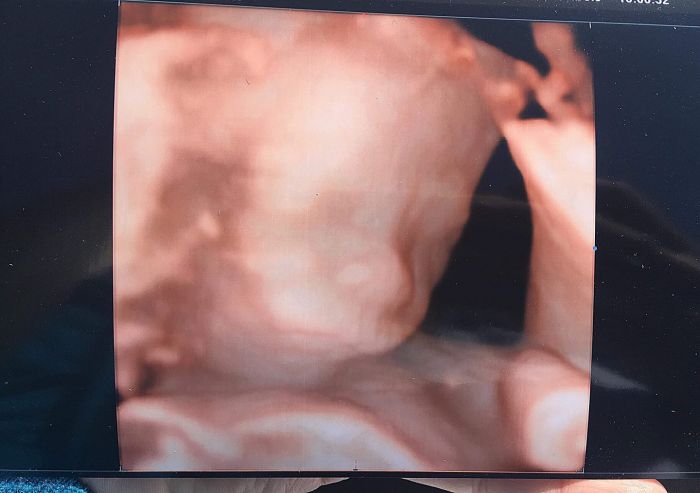

Zdravim Vas holky, po delsi dobe teda. Tak jak Se Vam dari? U me celkem v pohode, jen me to vedro asi znici ťza chvili. K dnesnimu dni mam nahore uz 20 kg noooo, ale mam dojem,ze pribiram i ze vzduchu. Nicmene,nejak to nehrotim. U dcery jsem pribrala 30 a za pul roku to bylo dole,takze se nebojim, ze by mi to zustalo. Dnes jsem 31+4 tt, prdus roste jako z vody,na posledni kontrole na gynde (30+1) mel, dle UZV, cca 1720g, takze to vypada,ze to bude fakt kluk jako buk. Vsechny testy apod. jsem mela v poradku,az teda na posledni KO. Mam trochu nizsi hladinu zeleza,takze do porodu do sebe musim hazet zelezo v tabletkach no. Ale jinak je ,diky bohu, vse v poradku. Prikladam fotku z UZV,je teda z 18.4., ale to nevadi. Jak jinak prozivate leto? Zatim se mejte krasne